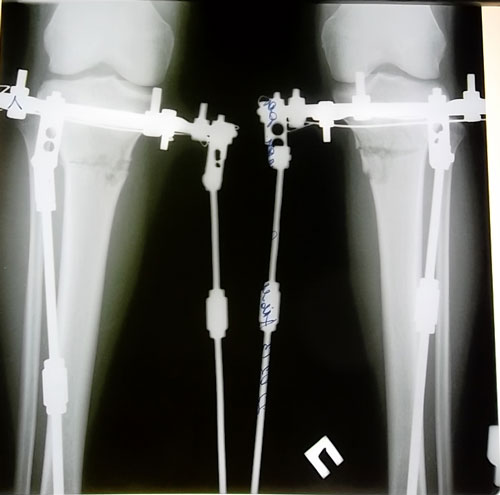

- Диагноз: О- образная деформация нижних конечностей